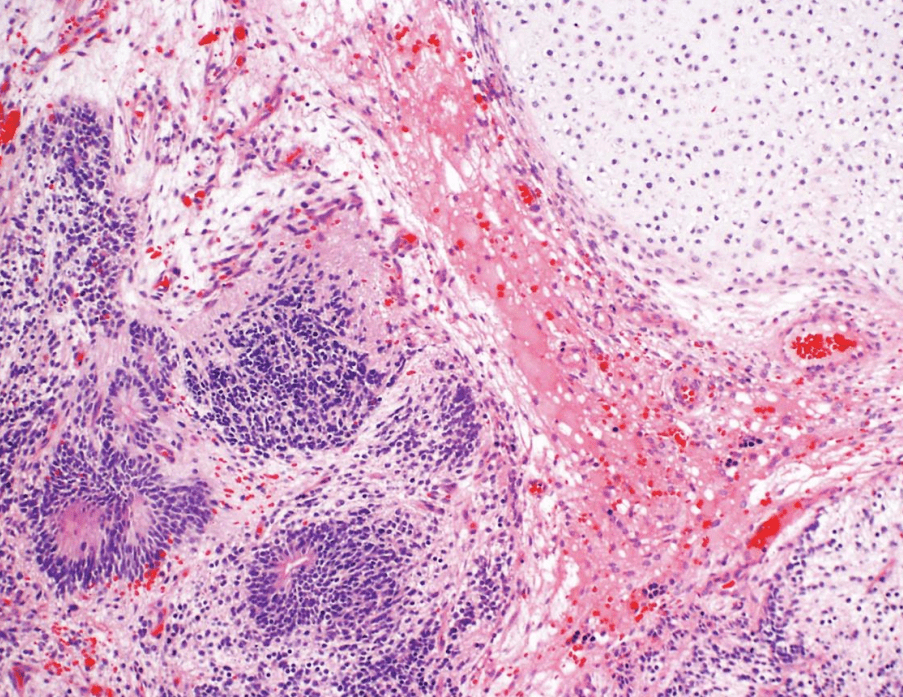

lung adenocarcinoma